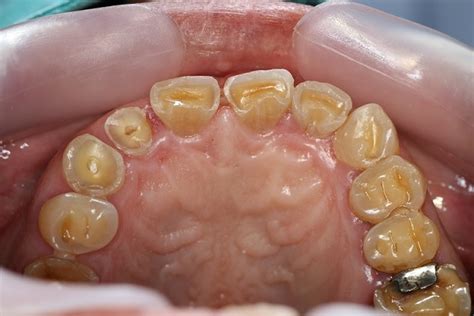

تآكل الأسنان (Dental Erosion) هو فقدان تدريجي في الطبقة الخارجية الصلبة من السن، والتي تُعرف باسم المينا، نتيجة التعرض المتكرر للأحماض.

خلافًا للتسوّس الناتج عن البكتيريا، فإن التآكل الحمضي يحدث بسبب أحماض مباشرة من الطعام والشراب، أو حتى من داخل الجسم (مثل أحماض المعدة).

• تغيّر لون الأسنان إلى الأصفر (بسبب انكشاف العاج تحت المينا)

• مظهر الأسنان "المصقول" أو اللامع بشكل غير طبيعي

• تشققات صغيرة أو تسطّح أطراف الأسنان الأمامية